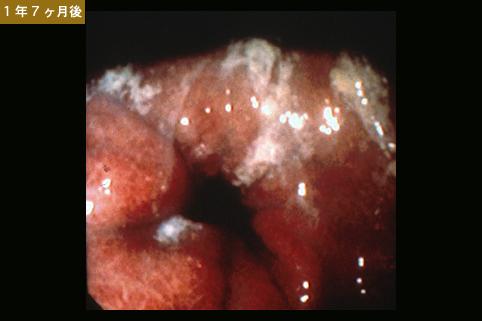

Criteria of Hist.ClassificationMalignant epithelial tumor/Signet-ring cellcarcinoma

LocationStomach/More than one of above

Technique, MethodEndoscopy

Macroscopic TypesType 4 Diffusely infiltrating type/

Size40 -

Depth of Tumor Invasionserosa (adventitia)